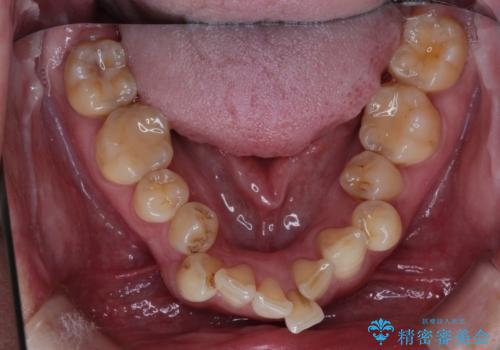

- 全体的なガタガタと前歯をきれいにしたいとのことで来院されました。

下の歯は重度のガタガタがあり、上の前歯は何本かが神経の治療がしてある状態でした。

インビザラインにて歯並びを整え、上顎の前歯にセラミックを装着する計画としました。